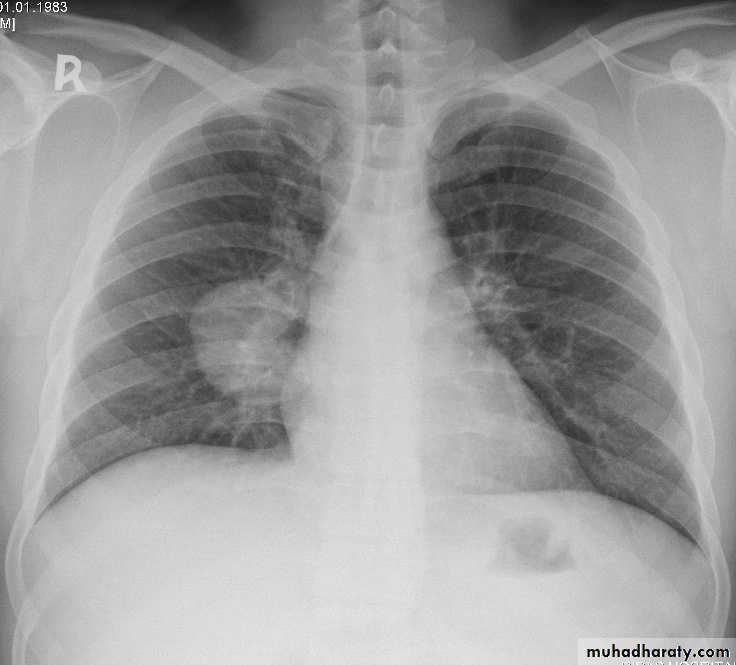

Lung cancer x rayPancoast Tumor